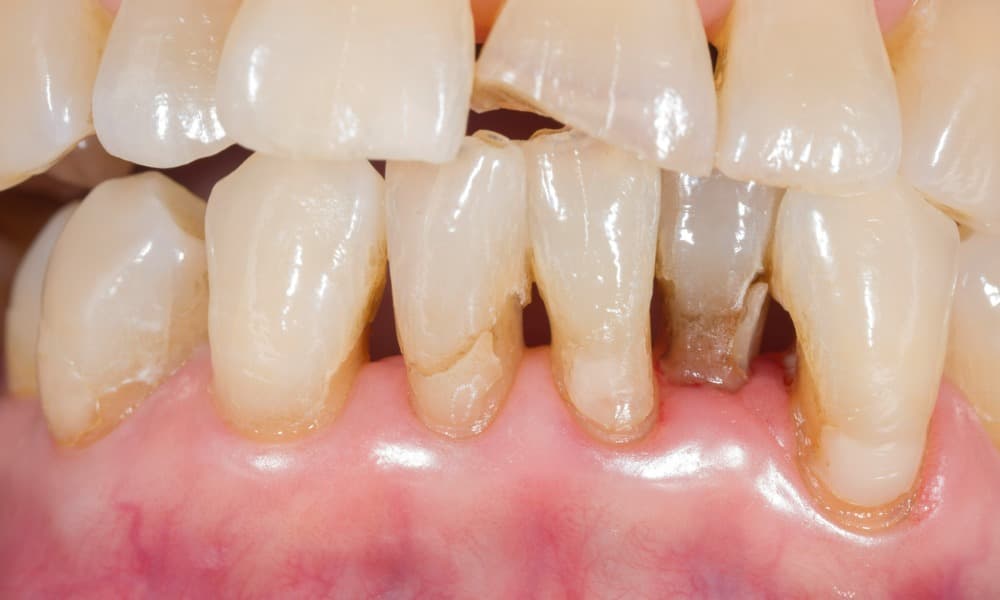

Long teeth occur primarily due to gum recession, where the gums recede due to periodontitis, tobacco use, or aggressive brushing, exposing more of the tooth’s root. They can be aesthetically unpleasing, cause long-term dental problems, and make basic oral care challenging.

- Increased sensitivity to temperature, pressure, and sweet or sour foods: Receding gums exposes the tooth’s root, which is more sensitive than the crown. A worn-out enamel can also expose the dentin, which is sensitive to temperature and pressure changes.

- Difficulty cleaning: Long teeth can be hard to clean because of their size and exposed root. Plaque can build up in the long crevices of the tooth, increasing the risk of gum disease, tooth decay, and infection.

- Tooth decay: Long teeth can be difficult to clean, and plaque can build up on the long crevices of the tooth. This increases the risk of tooth decay, cavities, and infection. Tooth decay occurs when acid from plaque erodes the enamel and dentin.

- Gum disease: Gum recession exposes more of the tooth’s root, increasing the risk of gum disease and infection. This can lead to long-term problems such as tooth loss, bad breath, and systemic diseases like heart disease, stroke, and diabetes. Gum disease starts as gingivitis – an inflammation of the gums that can cause redness and swelling. This can progress to periodontitis if left untreated, causing bone loss and long-term damage.

- Sensitivity: Root exposure makes long teeth more sensitive to temperature, pressure, and acidic foods, leading to discomfort and pain. Eating and drinking hot or cold items can be especially painful.

- Bone loss: Bacteria build-up and long-term damage can lead to severe jaw bone deterioration, leading to long-term problems such as shifting teeth, facial distortion, and misalignment.